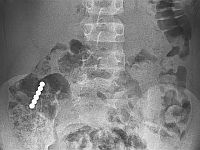

Опубликовано имя одного из подозреваемых в имплантации пациенткам яйцеклеток с гемофилией

Разрешено к публикации имя одного из подозреваемых в имплантации женщинам недоброкачественных донорских яйцеклеток: это эксперт в области репродуктивной медицины профессор Давид Бидер. Имя второго подозреваемого пока запрещено к публикации.